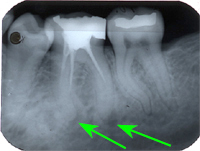

Ein 32 Jahre alter Mann kommt im November 1984 mit Zahnweh am unteren linken, zweithintersten Molaren (Backenzahn) in die Praxis. Das Röntgenbild von Abb. 1 zeigt insuffiziente Wurzelfüllungen bei allen drei Wurzelkanälen und an den Wurzelspitzen sogenannte Granulome, sichtbar als schwarze Flecken (grüne Pfeile in Abb. 1).

Therapie: Der Patient möchte den Zahn erhalten. In einem kurzen Gespräch erkläre ich die Ursache des Zahnwehs (insuffiziente Wurzelbehandlung) und die Behebung des Leidens mit folgenden Therapieschritten:

- Ausräumen der alten Wurzelfüllung mit mechanischen Instrumenten bis zur Wurzelspitze (Apex). Desinfizierende Einlagen.

- Sterile Wuzelfüllung aller Kanäle bis an die Wurzelspitzen des Zahnes (im Röntgenbild als weisse Linien in der Wurzelmitte sichtbar).